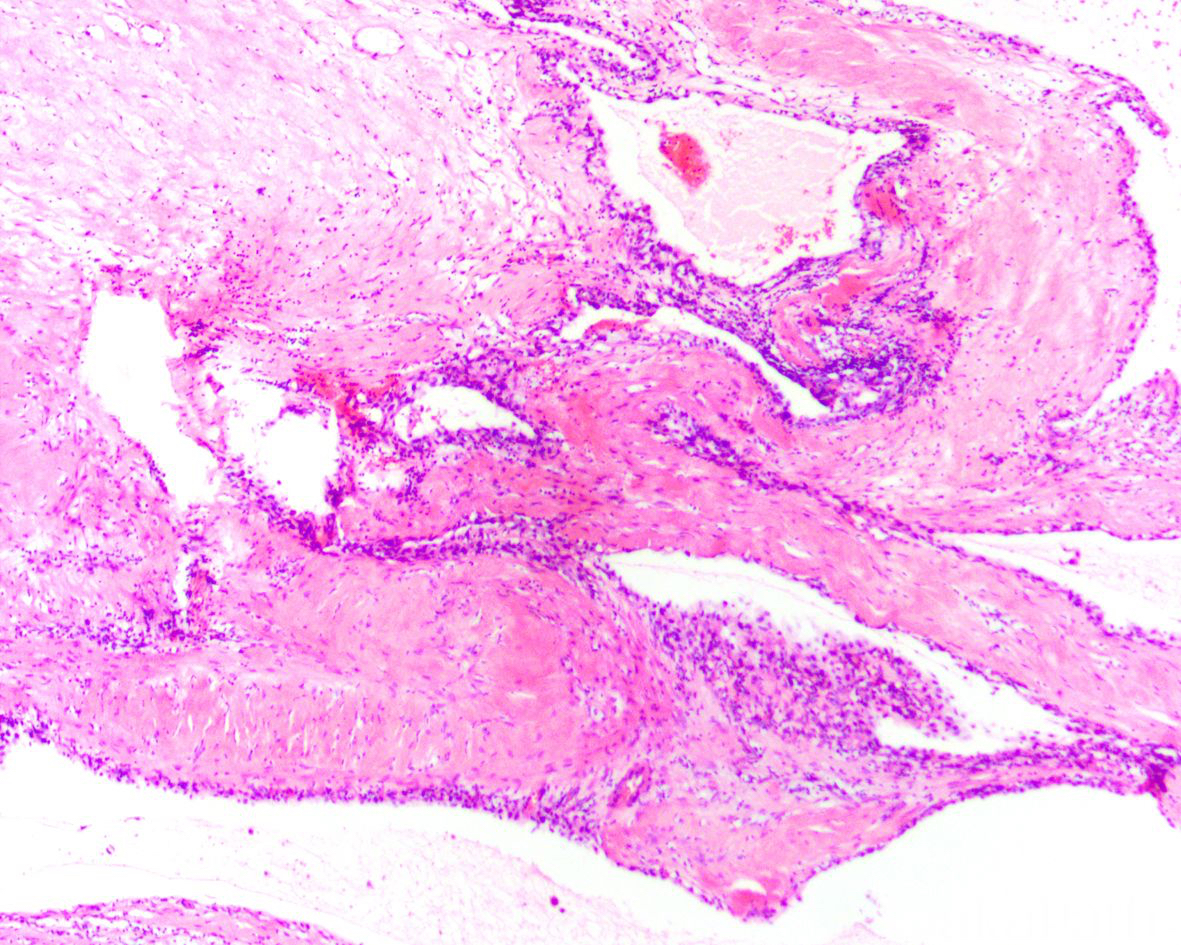

显示广泛囊性变和硬化性间质的透明细胞肾细胞癌

2,组织学上由多少不等的囊肿、硬化性间质以及实性透明细胞巢组成,以前两者为主;

3,囊肿被覆透明细胞,低倍镜下类似于低度恶性潜能多房囊性透明细胞肾肿瘤;硬化性间质可表现为富于肌纤维母细胞样间质伴含铁血黄素沉积(类似于肉芽组织)或疤痕样少细胞硬化性间质伴丰富的毛细血管网类似于毛细血管瘤,常见慢性炎细胞浸润,部分可见营养不良性钙化或骨化;实性透明细胞巢或单个散在的透明细胞常位于囊肿的间隔内或硬化性间质之中,有时需要免疫组化染色予以识别;

4,透明细胞的核级别多数为 ISUP1 或 2 级,少数为 3 级,无凝固性坏死。